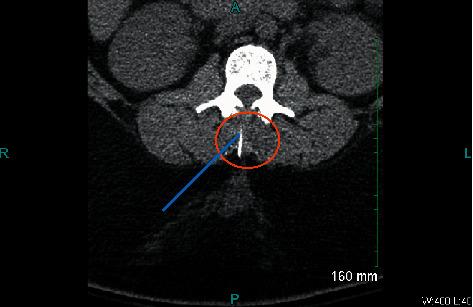

一位病态肥胖产妇在进行紧急剖宫产时发生脊柱穿刺针折断。

Broken Spinal Needle in a Morbidly Obese Parturient Presenting for Urgent Cesarean Section.

Neuraxial anesthesia has become the preferred method of anesthesia for nonemergent cesarean delivery and cases where regional anesthesia is not contraindicated. Multiple cases of broken spinal and epidural needles have been reported in the literature over the last several years; however, the specific incidence of needle breakage is still unknown. Less reliance on general anesthesia and increasing parturient body mass index (BMI) has likely contributed to more reports of broken needles during regional anesthesia for obstetric surgery. We describe a case of a broken spinal needle after attempted spinal anesthetic placement for cesarean delivery in a morbidly obese parturient, subsequent postoperative management, and current treatment recommendations.

神经轴索麻醉已成为非急诊剖宫产及区域麻醉无禁忌证情况下的首选麻醉方法。在过去几年的文献中已报道了多例腰麻和硬膜外穿刺针折断的病例;然而,针折断的具体发生率仍不清楚。对全身麻醉的依赖减少以及产妇体重指数(BMI)的增加,可能导致了产科手术区域麻醉期间更多针折断报告的出现。我们描述了一例病态肥胖产妇剖宫产术腰麻穿刺尝试后腰麻针折断的病例、后续的术后处理以及当前的治疗建议。